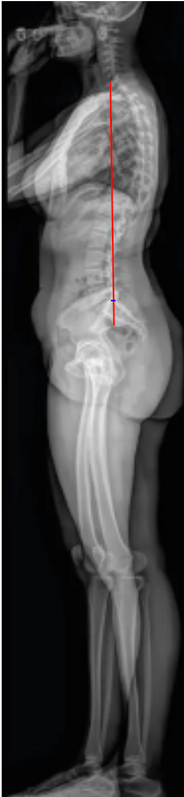

Sagittal Vertical Axis (SVA)

The Sagittal Vertical Axis (SVA) is the most widely used radiographic parameter to evaluate global sagittal balance.

It measures the horizontal offset between the C7 vertebral body plumb line and the posterior–superior corner of the sacrum (S1) on a standing lateral full-length spine X-ray.

SVA represents the anterior or posterior translation of the thoracic cage and head relative to the pelvis and is a key determinant of posture, energy expenditure, and compensatory mechanisms in spinal deformity.

• Drop a vertical plumb line from the center of the C7 vertebral body straight downward, parallel to the gravitational vertical.

• Measure the horizontal distance (in millimeters) between the C7 plumb line and the posterior–superior corner of S1.

• If the C7 plumb line lies anterior to S1, the SVA is positive.

• If it lies posterior to S1, the SVA is negative.